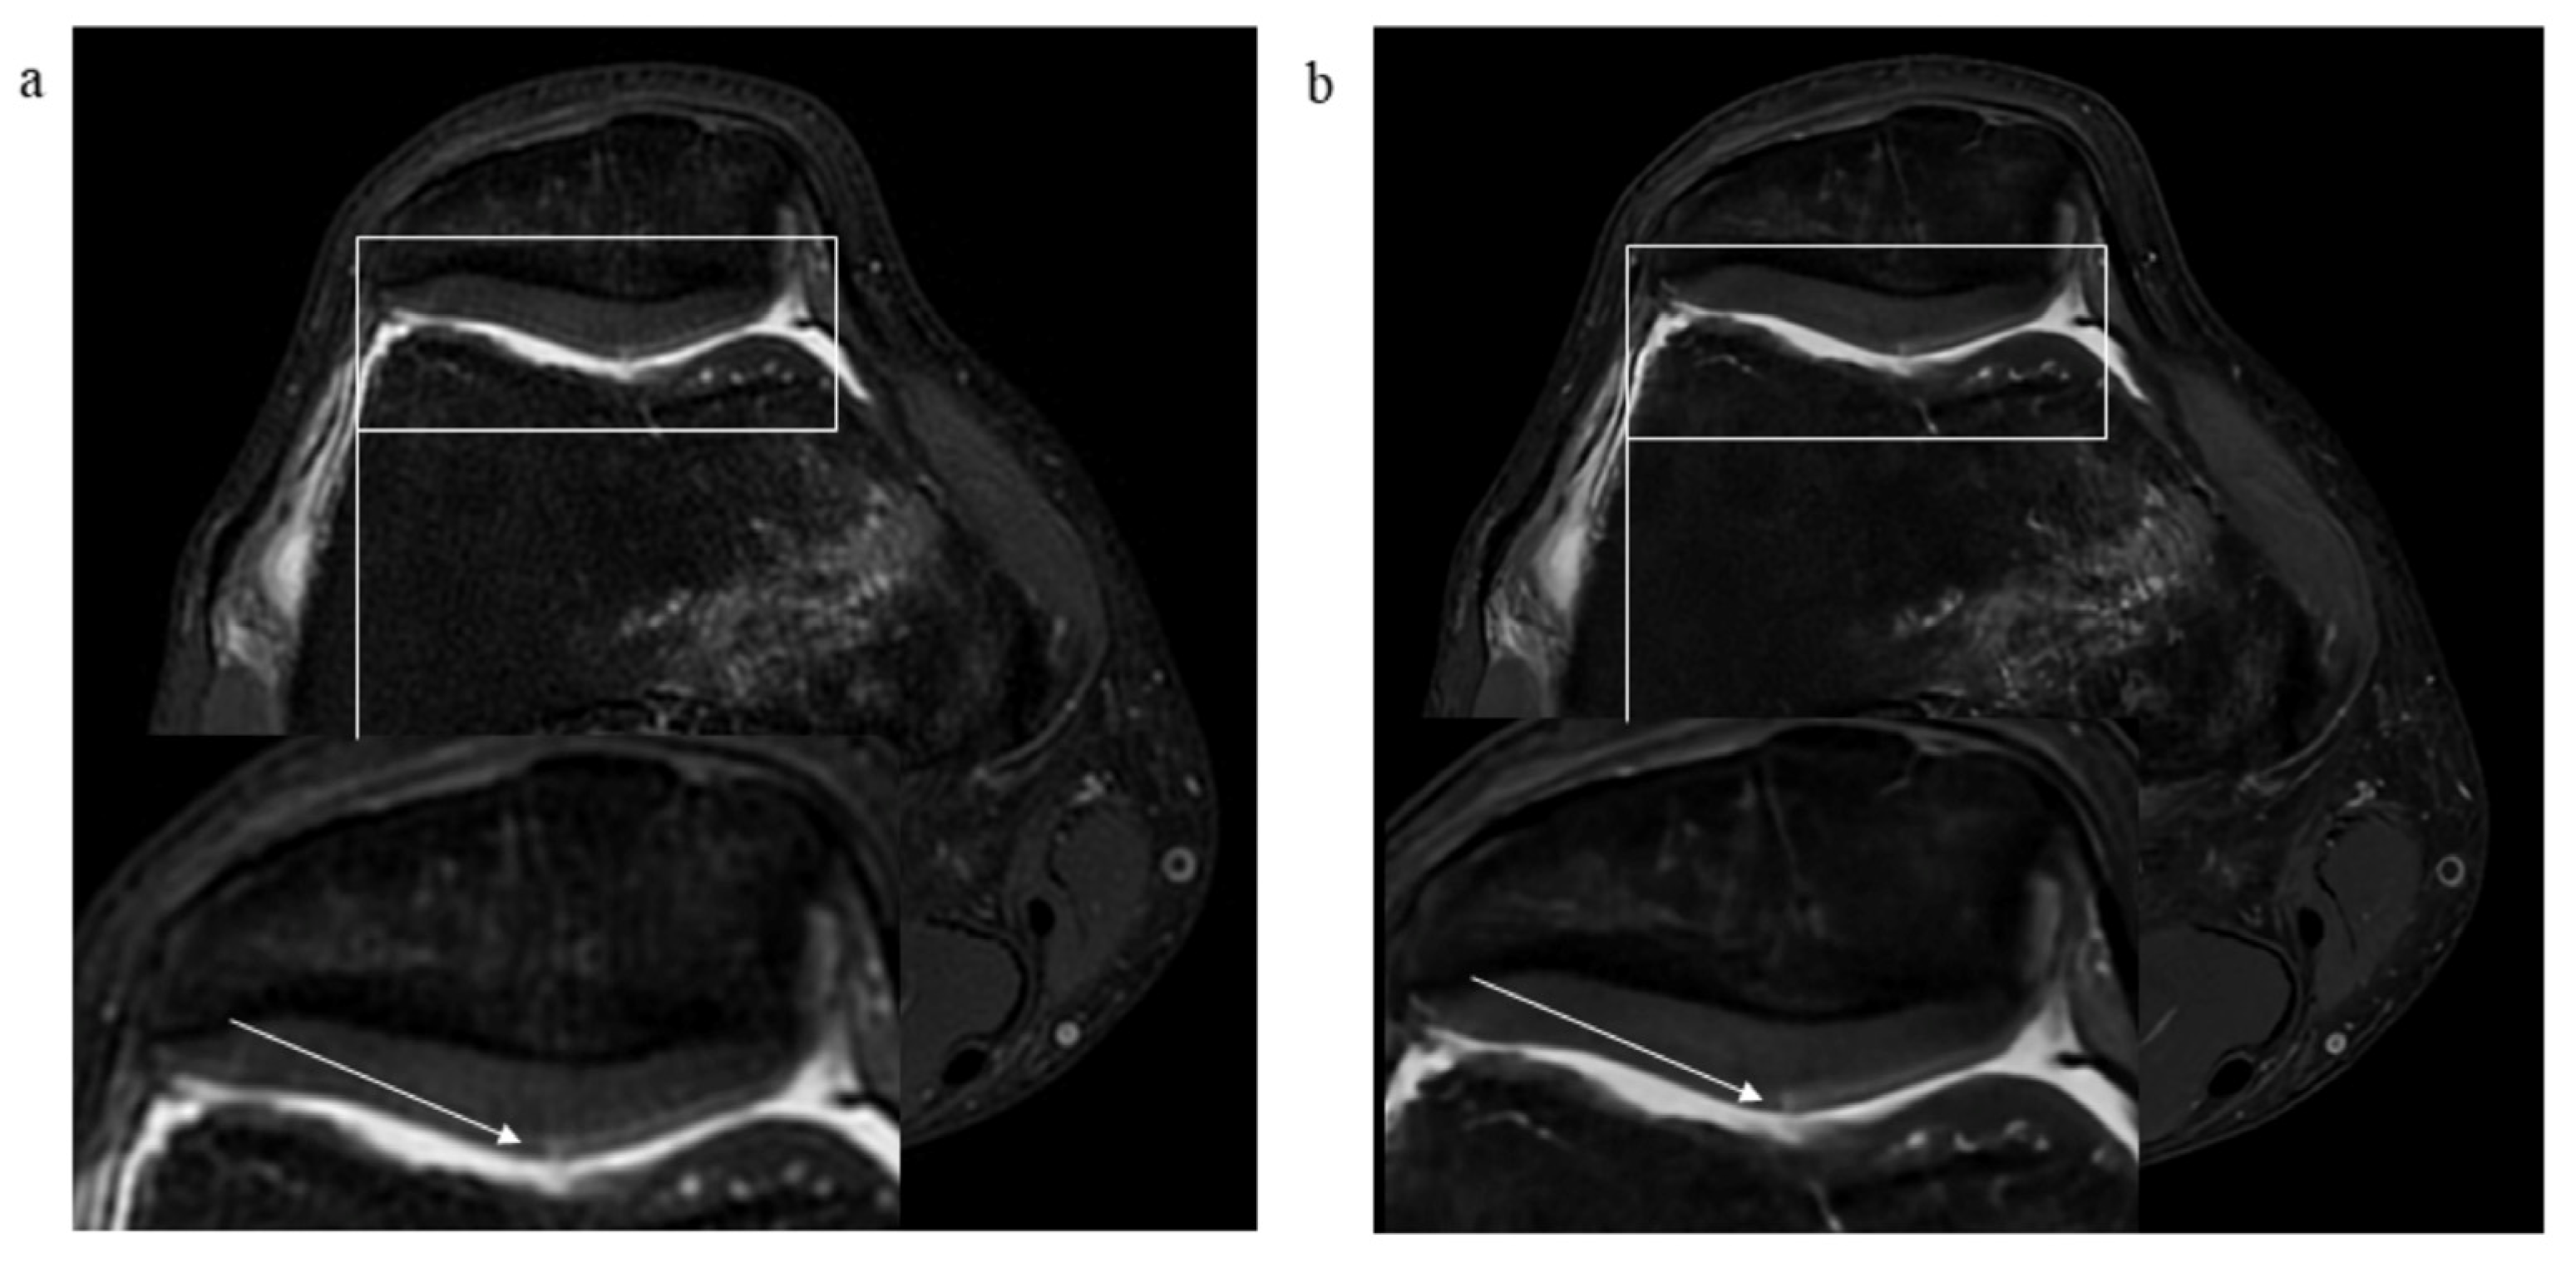

3.2. Pathological Findings

3.3. Signal-to-Noise and Contrast-to-Noise Ratios